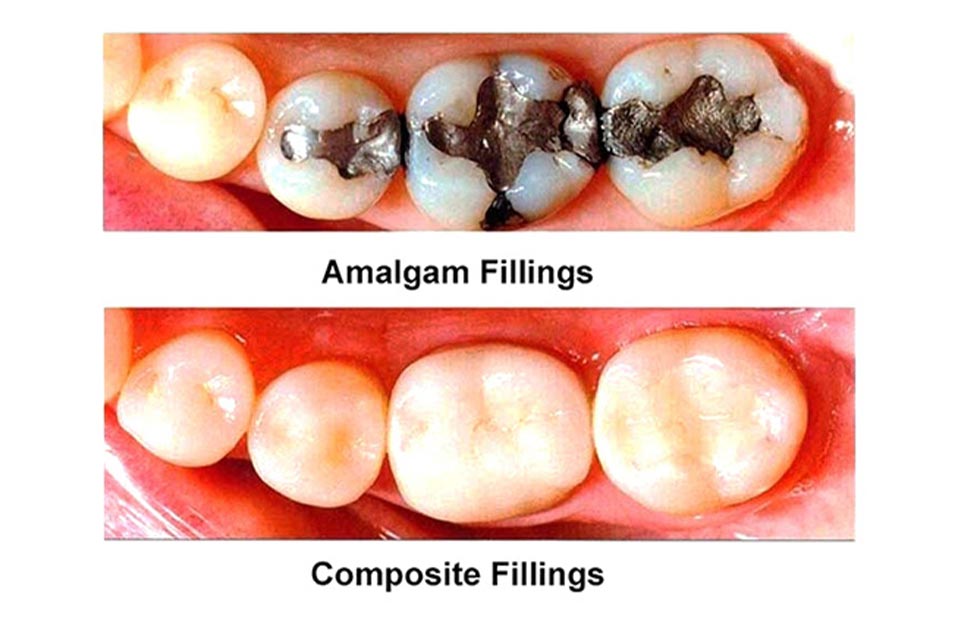

آمالگام : آمالگام از رایجترین و مورد استفاده ترین مواد پر کننده دندان ها است .

کامپوزیت دندان : کامپوزیت دندان نوعی ماده پر کننده همرنگ دندان است که به خوبی دندان را پر می کند هزینه پر کردن دندان با کامپوزیت دندان زیاد است و ماندگاری آن نیز کمتر است .